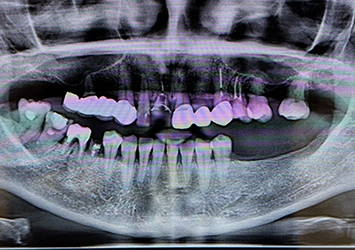

治療前写真 恵比寿南DENTAL 治療前写真 恵比寿南DENTAL 治療前写真 恵比寿南DENTAL

施術内容

【30代男性】

生え代わらず晩期残存した左下の乳歯を抜歯しインプラントを埋入

治療期間

4ヶ月

リスク

術中の不可抗力によるトラブル(出血など)、術後注意事項を守らないことによる疼痛、感染、上部構造装着後口腔内清掃を怠ったことによるインプラント周囲組織の炎症

副作用

治療後の口腔内清掃、及びメインテナンスを怠ったことによるインプラント周囲粘膜炎またはインプラント周囲炎

費用

インプラント埋入:30万円 × 2本

ジルコニアクラウン:12万円 × 2本